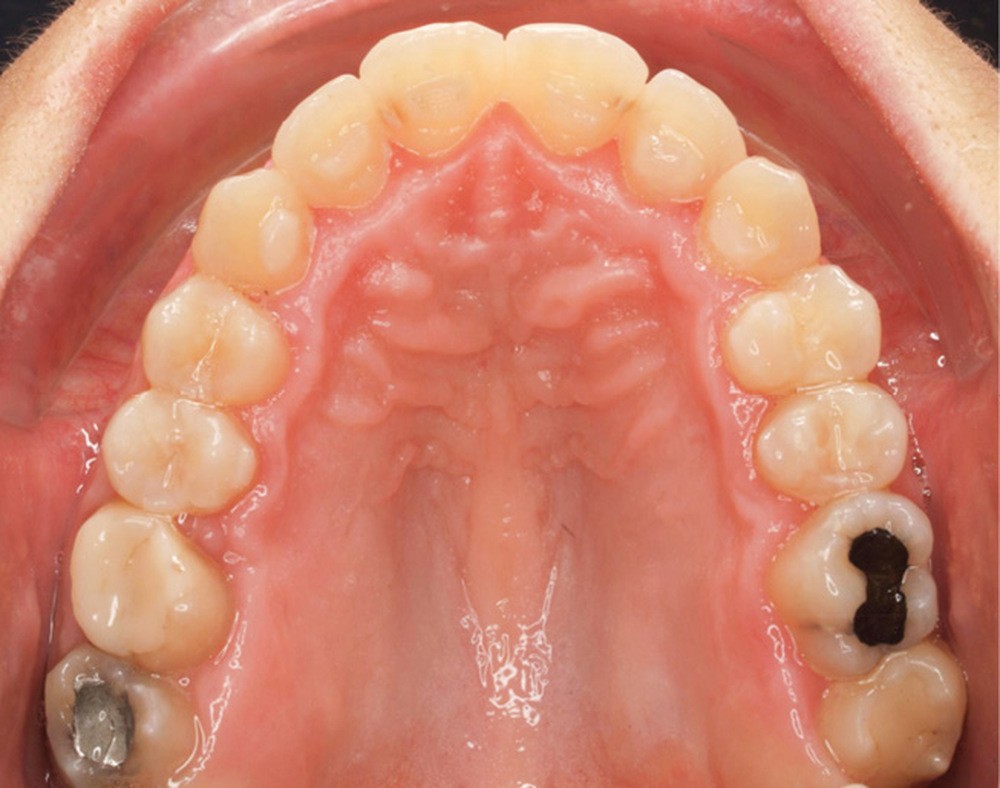

Diagnostic (fig. 1a-g)

La patiente présente une classe III squelettique dans un contexte hyperdivergent associée à une endoalvéolie maxillaire, un articulé inversé antérieur, une rétroversion incisive maxillaire, des rapports de classe I canine bilatérale, une absence de 16 et 36.

Au niveau esthétique, le profil est rectiligne. La lèvre supérieure est plus effacée, en retrait par rapport à la lèvre inférieure. De face et de profil, la mandibule paraît massive et le maxillaire effacé : le manque de soutien de la lèvre supérieure contribue à cette impression.

Le sourire est étroit, dégradé par les malpositions dentaires.

Au niveau fonctionnel, il existe un pro-glissement mandibulaire et un articulé inversé antérieur. Le profil téléradiographique montre en occlusion des rapports labiaux et un profil de classe III plus marqué que sur photographies.